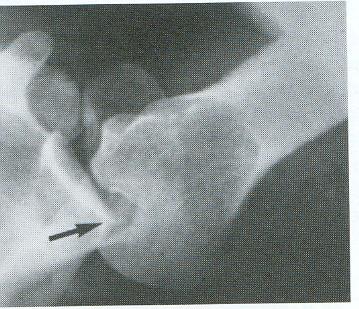

Artrografía…

Indicaciones de la Artrografía • Ruptura del Maguito de los Rotadores • Capsulitis Adhesiva • Alteraciones del Tendón del Bíceps • Luxaciones Crónicas • Evaluación de Inflamación Sinovial • Hombro Congelado

Artrografía